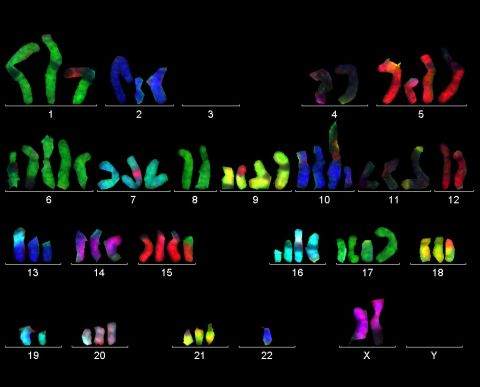

Le indicazioni che possono portare alla richesta da parte del ginecologo di effettuare una funicolocentesi possono essere dovute a dei risultati dubbi dell’amniocentesi, alla necessità di conoscere in tempi rapidissimi la mappa cromosomica del bambino (sospette malformazioni o sofferenza fetale) oppure al fatto che avendo la gestante già raggiunto le ventuno–ventidue settimane non ci sia tempo per aspettare i risultati di un’amniocentesi se si dovesse presentare l’eventualità di un aborto terapeutico nei tempi della legge 194. La funicolocentesi infatti restituisce i risultati in modo molto più veloce dell’amniocentesi.